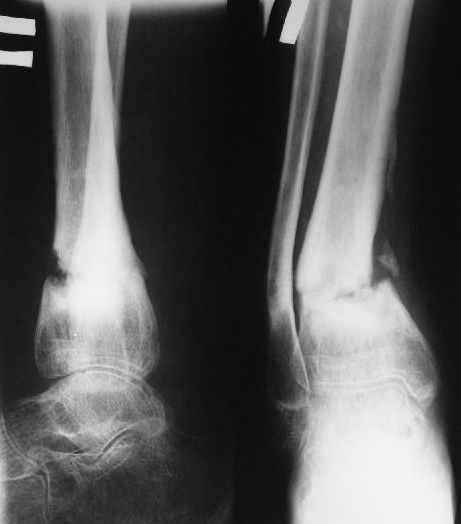

В январе 2005: варусная деформация н\3 голени, болевой с-м, комбинированная контрактура г\стопного сустава, нейропатия м\берцового нерва сохраняется слабость разгибания 1 пальца.

Операции: 1 Клиновидная резекция на вершине деформации м\берцовой кости.

2 Тугоподвижный ложный сустав н\3 б\берцовой кости. Рубцы выполняющие пространство между отломками, канал проксимального отломка иссечены.

Одномоментное устранение деформации, остеосинтез Г-образной пластиной.

Так как речь зашла непосредственно о травме, см этапные

снимки. Как все было